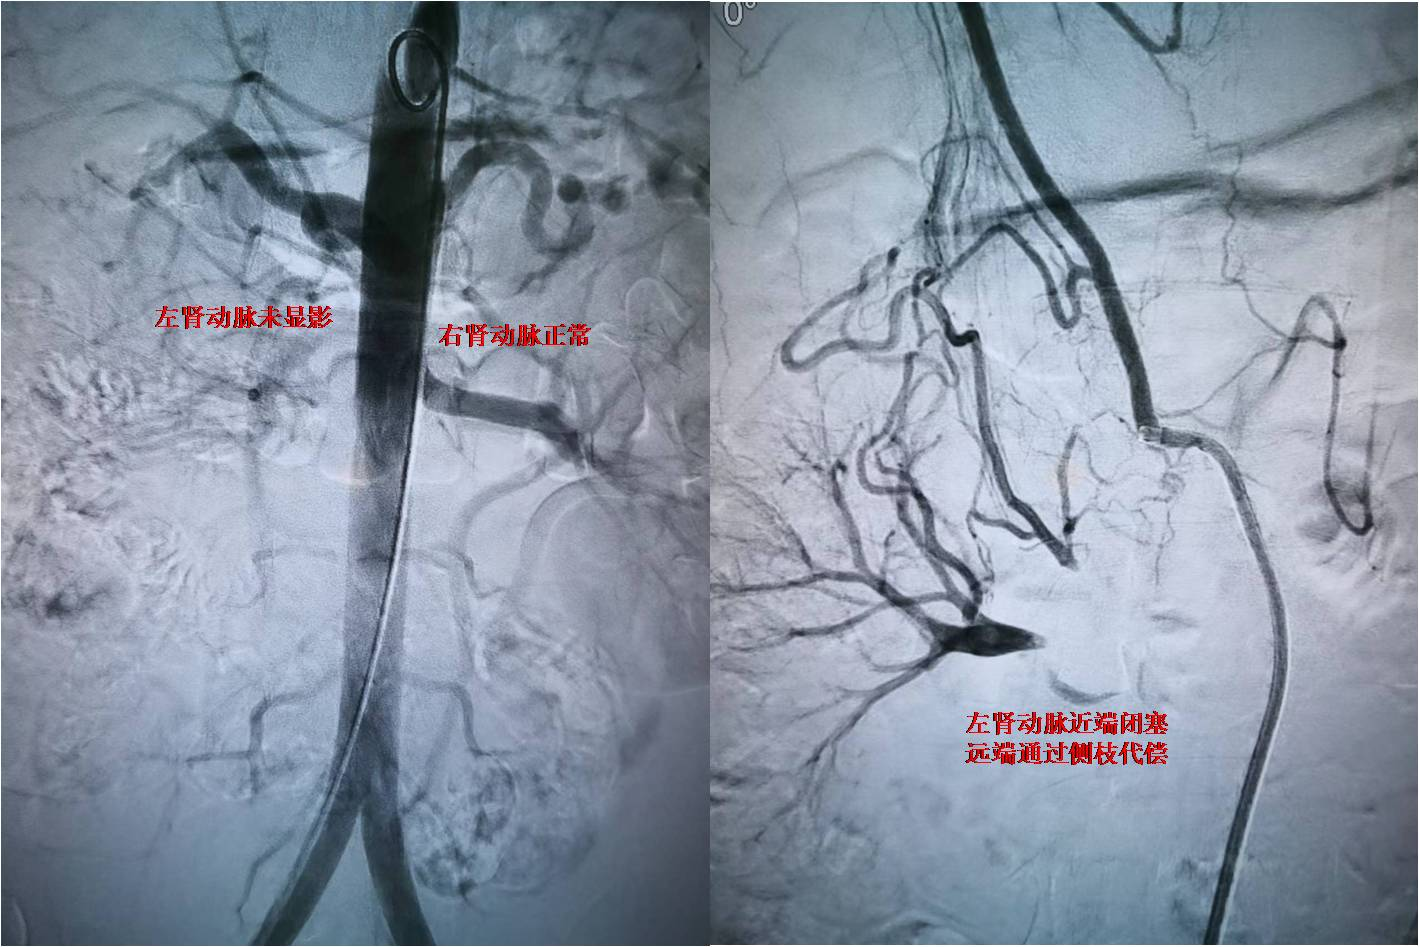

图-1 闭塞的肾动脉

患者为未成年男性,在当地因高血压病就诊检查,发现存在肾动脉狭窄可能,患者血压最高达200/146mmHg,为进一步诊治,来到西安交大一附院血管外科杨林教授门诊。患者入院后,杨林教授及诊疗团队韩阳医师、武士琪医师、李小兵医师对其进行了完善的术前检查、术前准备及药物治疗。进一步明确患者为肾动脉闭塞,手术难度极大,手术风险极高。考虑到患者未成年,为保留患者潜在的肾功能,同时避免采用常规的金属支架技术,杨林教授团队经过详细的术前讨论和设计手术方案后,决定给患者实施局麻微创的药物球囊成型技术。在介入手术室的配合下,发现患者为右肾动脉闭塞,远端通过毛细血管代偿,手术团队通过精细的微创技术,反复尝试都未能通过闭塞段血管,最后通过各种微导丝、微导管技术的联合应用终于通过闭塞的肾动脉,然后通过小球囊预扩张,过渡到常规球囊扩张,最后为患者实施药物球囊扩张成形术,患者闭塞的肾动脉得到完美重建。患者术后在血管外科医护团队的严密监控下顺利恢复。术后血压即恢复正常,于近日顺利出院。